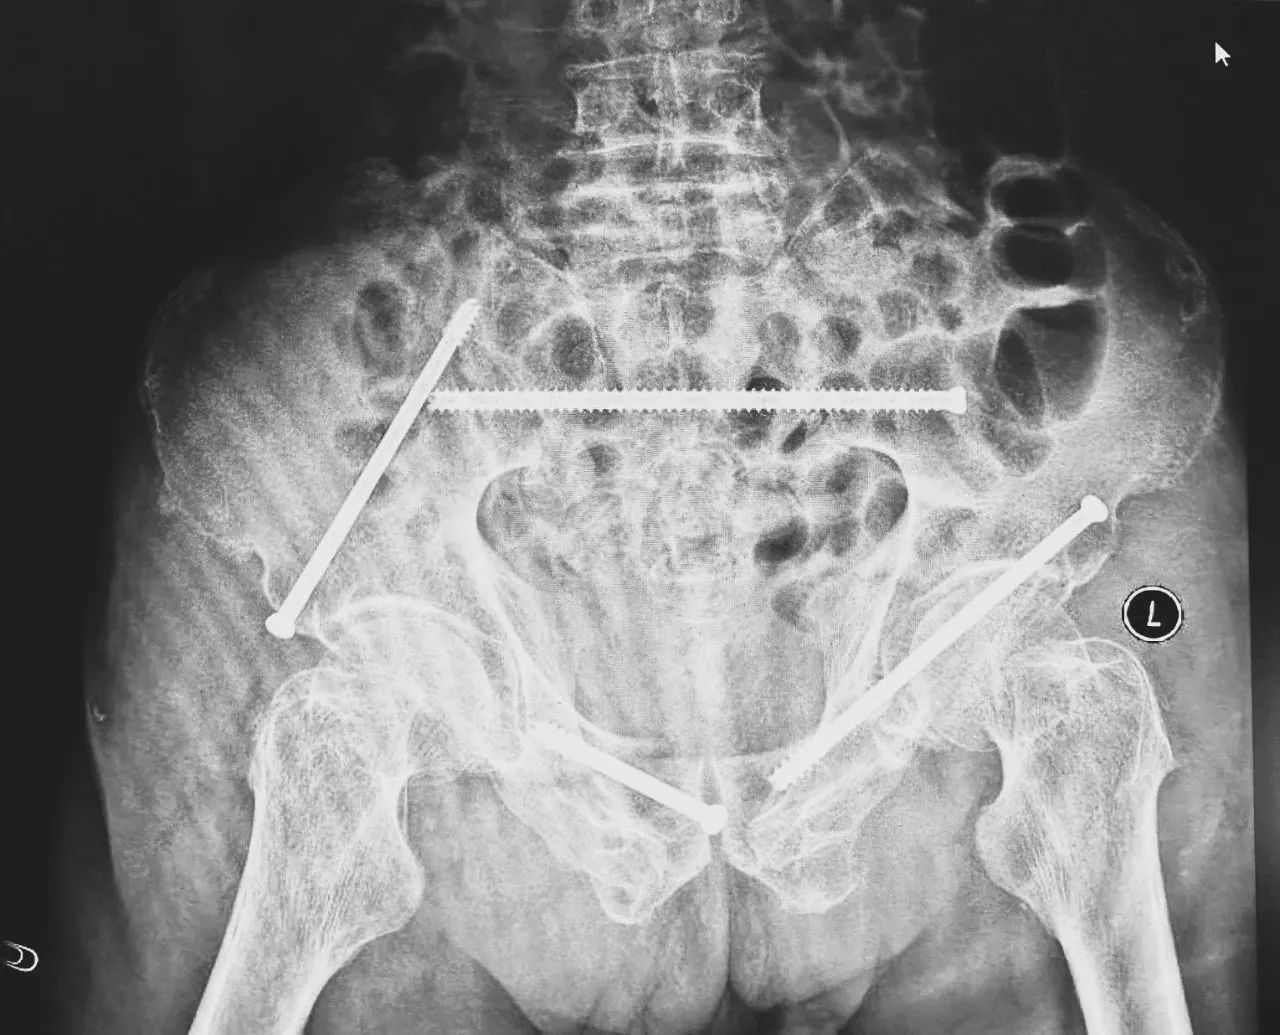

ÎÞÓ°µÆÏ£¬£¬£¬£¬£¬£¬£¬ÖÇÄܹǿÆÍŶӽ«»¼Õßʾ×ÙÆ÷£¬£¬£¬£¬£¬£¬£¬·ÅÔÚ×ó²à÷ÄǰÉϼ¬£¬£¬£¬£¬£¬£¬£¬Ê¹ÓÃÊõÖÐÈýάӰÏñ×°±¸»ñÈ¡¹ÇÅèµÄÈýάͼÏñ£¬£¬£¬£¬£¬£¬£¬É¨ÃèЧ¹û´«ÊäÖÁ»úеÈ˵¼º½ÏµÍ³£¬£¬£¬£¬£¬£¬£¬Íê³ÉÂݶ¤ÖÃÈëµÄλÖúÍ×ßÐΣ¬£¬£¬£¬£¬£¬£¬²¢ÔÚ»úеÈ˵ÄÖ¸µ¼Ï»®·ÖÖÃÈë4öͨµÀÂݶ¤¡£¡£¡£¡£¡£¡£ÖÃÈëºóÔٴξÙÐÐCTɨÃèÑéÖ¤£¬£¬£¬£¬£¬£¬£¬Ö¤Êµµ¼Õë׼ȷÖÃÈë¡£¡£¡£¡£¡£¡£

ÔڹǿÆÊÖÊõ»úеÈ˺ÁÃ×¼¶¾«¶ÈµÄÖ¸µ¼Ï£¬£¬£¬£¬£¬£¬£¬ÕâÏîÔ±¾¸ßÄѶȡ¢¸ßΣº¦µÄÊÖÊõ±äµÃÔ½·¢¾«×¼¸ßЧ¡£¡£¡£¡£¡£¡£ÊÖÊõ¹²¼ÆºÄʱ1¸ö°ëСʱ£¬£¬£¬£¬£¬£¬£¬ÊõÖгöѪ²»µ½20ºÁÉý£¬£¬£¬£¬£¬£¬£¬Ã¿Ã¶Âݶ¤ÖÃÈëλÖõÄÇпڳ¤¶ÈÔ¼1.5ÀåÃ×£¬£¬£¬£¬£¬£¬£¬ÍêÉÆµÖ´ïÁËÔ¤ÆÚ¡£¡£¡£¡£¡£¡£Êõºó£¬£¬£¬£¬£¬£¬£¬Íõ´óÒ¯Çå¾²·µ»Ø²¡·¿¡£¡£¡£¡£¡£¡£

ÊõºóµÚ¶þÌ죬£¬£¬£¬£¬£¬£¬Ò½ÉúÍŶӸ´²éXƬÏÔʾÂݶ¤Ö²ÈëλÖúÜÊÇÖª×㣬£¬£¬£¬£¬£¬£¬¹ÇÕÛ»ù±¾µÖ´ïÎȹ̸´Î»£¬£¬£¬£¬£¬£¬£¬Í¬Ê±£¬£¬£¬£¬£¬£¬£¬¸´²éµÄȫѪϸ°û¼ÆÊýÖУ¬£¬£¬£¬£¬£¬£¬ÑªºìÂѰ×Ö¸ÊýΪ102g/L¡£¡£¡£¡£¡£¡£ÊõºóµÚÈýÌ죬£¬£¬£¬£¬£¬£¬ÔÚÖÇÄܹǿƲ¡·¿Õչ˻¤Ê¿ÍŶӼ°¿µ¸´Ê¦µÄÖ¸µ¼ºÍÕչ˻¤Ê¿Ï£¬£¬£¬£¬£¬£¬£¬Íõ´óÒ¯¿ÉÒÔ×øÁ¢ÔÚ´²ÉÏ¡£¡£¡£¡£¡£¡£ÊõºóµÚËÄÌ죬£¬£¬£¬£¬£¬£¬Íõ´óÒ¯ÓÀ´Á˳öÔºÈÕ£¬£¬£¬£¬£¬£¬£¬¡°µÃ¿÷ÓÐÁËÕâôÏȽøµÄÒ½ÁÆÊÖÒÕ£¬£¬£¬£¬£¬£¬£¬ÈÃÎÒ»¹ÄÜϵØÐÐ×ߣ¬£¬£¬£¬£¬£¬£¬Ð»Ð»ÄãÃÇ£¡¡±